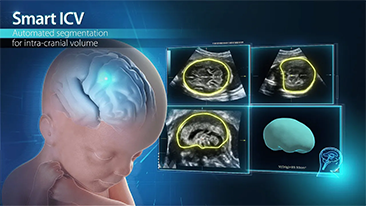

Kad?n sa?l??? tarama ziyaretlerinde yĂŒksek dĂŒzeyde hasta hacimlerini desteklemek i?in, optimize edilmi? OBG i? ak??lar? gerekir. ?rne?in, merkezi sinir sistemi (CNS) malformasyonlar?, en yayg?n g?rĂŒlen konjenital anormalliklerden biridir. K?tĂŒ fetĂŒs pozisyonu gibi, ?e?itli g?rĂŒntĂŒleme durumlar? nedeniyle, 2 boyutlu ultrasonda MSPâyi elde etmek ?zellikle zordur. Bu nedenle, otomatik alg?lama ve ?l?ĂŒmler, tarama verimlili?ini bĂŒyĂŒk ?l?ĂŒde art?rabilir.